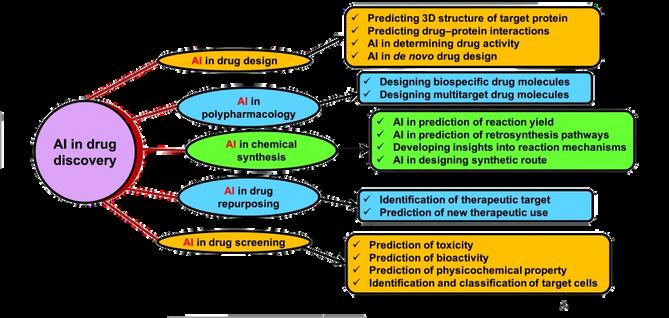

The pharmaceutical business has undergone a transformation that is nothing short of revolutionary as a direct result of the integration of artificial intelligence into drug discovery and development. This has resulted in an acceleration of the sector's overall growth In this article, we will explore areas of integration, tools and approaches used in the enforcement of AI, current obstacles, and potential solutions to those challenges. In the pharmaceutical industry, data digitization has increased dramatically in recent years However, the difficulty of gathering, evaluating, and utilising knowledge to solve complicated healthcare problems arises with digitalization. This encourages the adoption of AI, which can manage massive amounts of data with greater automation AI is a technology-based system that use a variety of advanced tools and networks to simulate human intellect. At the same time, it does not threaten to totally replace human physical presence. AI employs systems and software that can read and learn from input data in order to make independent judgments for achieving certain goals.

Drug discovery and development are two of the most important translational scientific activities that contribute to human health and well-being. However, developing a novel medicine is a hard, costly, and time-consuming procedure. The combination of artificial intelligence (AI) with new experimental technologies is intended to improve the search for novel drugs faster, cheaper, and more effective.

In spite of its many benefits, artificial intelligence (AI) is currently confronted with a number of significant data challenges, including the scale, growth, diversity, and uncertainty of the data. The data sets that pharmaceutical companies have available for drug development can involve millions of compounds, and the traditional ML tools that are used may not be able to handle the complexity of this type of data. A computational model that is based on the quantitative structure-activity relationship (QSAR) can quickly predict large numbers of compounds or simple physicochemical parameters like log P or log D On the other hand, these models are a long way from being able to predict more complicated biological properties, such as the efficacy and adverse effects of compounds In addition, models that are based on QSAR are plagued by issues such as having insufficiently large training sets, having experimental data in training sets that is inaccurate, and not having sufficient experimental validations. The recently developed AI approaches, such as deep learning (DL) and relevant modelling studies, which can be implemented for safety and efficacy evaluations of drug molecules based on modelling and analysis of big data, can help overcome the challenges that have been presented here. Various AI tools are being used to aid in all four stages of the drug development process (basic research for drug discovery; pre-clinical phase; clinical phase; and postmarketing).

Identifying molecular targets, searching for hit and lead compounds, synthesising drug-like compounds, and predicting ADME-Tox are some of the main tasks where AI has proven useful. On the one hand, this review brings a mathematical vision of some of the key AI methods used in drug development closer to medicinal chemists, while on the other hand, it brings the drug development process and the use of various models closer to mathematicians The emphasis is on two aspects that are not covered in other surveys: Bayesian approaches and their applications to molecular modelling, and the eventual final use of the methods to support decisions.